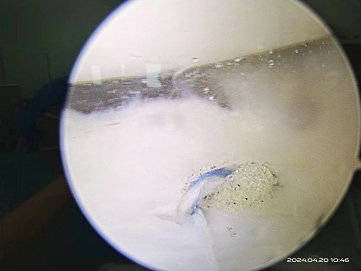

由于患者年轻,活动量大,且新鲜损伤,主任医师闫鹏为陈某实施了膝关节镜下半月板缝合修复术,手术仅需要做2个5mm小切口,术中直视下证实了患者半月板撕裂。手术非常顺利,最大程度保留了患者的半月板,且切口很小,不影响美观。

▲ 缝合后所见

在手术中首先会修整半月板的形态使之趋于正常平整的半环状结构,最后会使用半月板缝合器对修整的半月板进行牢固和稳定以解决半月板撕裂引起的膝关节疼痛和关节软骨磨损,避免骨关节炎等严重的晚期并发症。